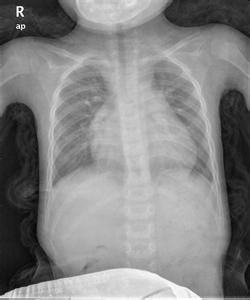

2、體徵:心前區搏動增強,由於右心室肥厚,出現明顯的心前區隆起。患者有明顯的呼吸困難,肝臟增大。患者多有心動過速,胸骨左緣第3、4肋間可聽診到3=-4級粗糙的收縮期雜音,心尖部可聽診到典型的房室瓣反流所引起的響亮的收縮期雜音,肺動脈瓣聽診區第二心音亢進明顯。

心電圖、胸片、超聲心動圖可明確診斷。右心導管檢查目前僅用於測定肺血管阻力,為判斷是否尚具有手術適應症提供依據。